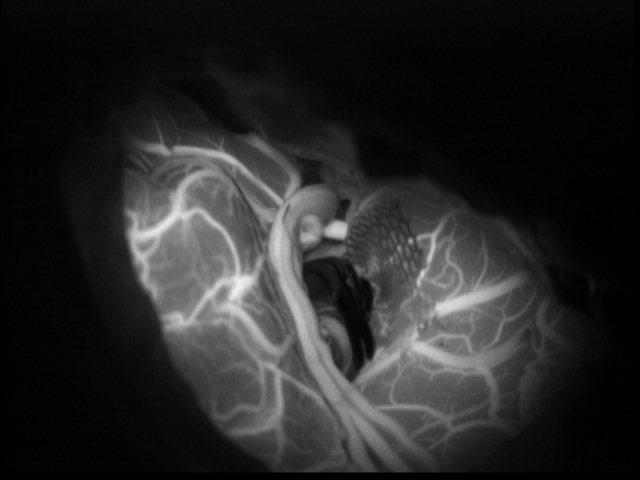

개두술 자체에 의한 합병증은 감염 및 수술 후 경막위/아래 혈종 등의 합병증이 발생 가능하나, 과거에 비하여 상당히 개선되었다. 개두술 후 근위축, 골손실로 인한 두상이 변형되는 문제가 있으나, 최근에는 절개부위가 최소화되고 성형재료를 사용하는 등 미용적인 측면에 대해서도 노력을 기울이고 있다. 동맥류 결찰에 관련된 위험 중 뇌경색은 모혈관의 협착 또는 분지혈관의 폐쇄에 의해 발생할 수 있으며, 영구적인 신경학적 장애를 유발할 수 있다. 이를 극복하기 위해 최근에는 유발전위(Evoked potential) 검사를 수술 중 시행하여 전신마취 중 운동 및 감각 기능의 변동 여부를 모니터링 하는 경우가 많다. 또한 수술 중 초음파로 혈류를 확인하고, 인도시아닌 형광 혈관조영술을 시행하여 혈류의 변화를 감지하고 동맥류로 들어가는 혈류가 차단된 것을 확인하는 과정을 거친다. 결찰 중 모동맥의 손상되는 경우도 발생할 수 있는데, 혈관 성형술이나 혈관 문합술을 시도할 수 있다. (그림) 인도시아닌 형광 혈관조영술: 동맥류 결찰 후에 시행하여 동맥류의 결찰 여부를 확인하고 혈류를 변화 여부를 확인한다.

인도시아닌 형광 혈관 조영술